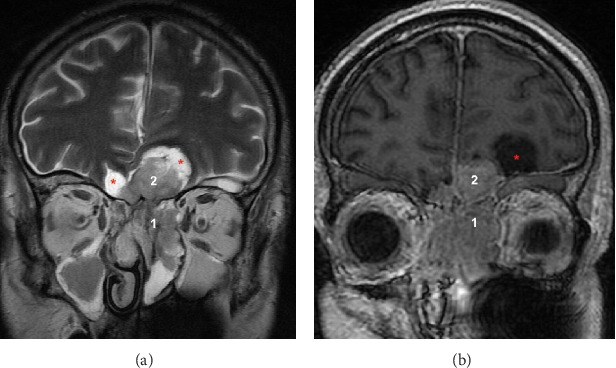

Background: Olfactory neuroblastoma (ONB) is a rare tumor of the nasal cavity. It may sometimes present with Cushing's syndrome due to adrenocorticotropic hormone (ACTH) secretion, making it challenging to diagnose. Methods: A 65-year-old man with hypokalemia and general weakness presented to the emergency department for Cushing's syndrome. Brain imaging revealed a tumor originating from the ethmoid bone with peritumoral cysts. The first biopsy suggested an ectopic corticotropic pituitary adenoma or a well-differentiated neuroendocrine tumor. However, the second biopsy confirmed an ONB, as suspected by the otolaryngologist. Treatment consisted of neoadjuvant chemotherapy, surgery, and radiotherapy. Results: The patient was cured of Cushing's syndrome and remained in remission at 10 years of follow-up. Conclusion: An unusual mode of discovering ONB is via the diagnosis of Cushing's syndrome caused by ACTH secretion, which may manifest throughout the course of follow-up. Imaging analysis and discussion with pathologists are essential to achieve an accurate diagnosis.